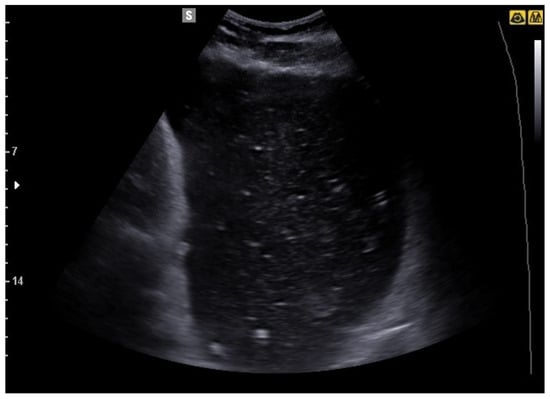

6. Bowel Obstruction

6.1. GIUS Signs of SBO